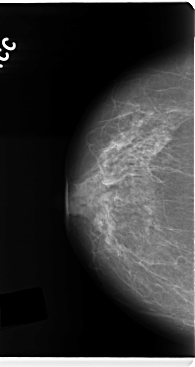

C_0133_1.RIGHT_MLO

RIGHT_CC LINES 4768 PIXELS_PER_LINE 2528 BITS_PER_PIXEL 12 RESOLUTION 50 NON_OVERLAY

RIGHT_MLO LINES 4704 PIXELS_PER_LINE 2520 BITS_PER_PIXEL 12 RESOLUTION 50 NON_OVERLAY